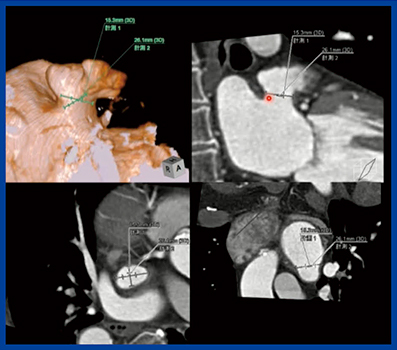

大動脈弁狭窄は,大動脈弁が狭窄し弁が開放されなくなる状態で,左室に圧負荷がかかり,駆出が正常に行われなくなり心不全を起こす。大動脈弁狭窄に対しては,10年以上前から経カテーテル的大動脈弁置換術(TAVI)が行われ広く普及している。心臓CTで弁輪径,弁栓の長さ,高さなどを計測して,留置する弁径の選択など術前のプランニングを立てることが重要である(図3)。

図3 大動脈弁狭窄での「TAVR術前プランニング」による解析